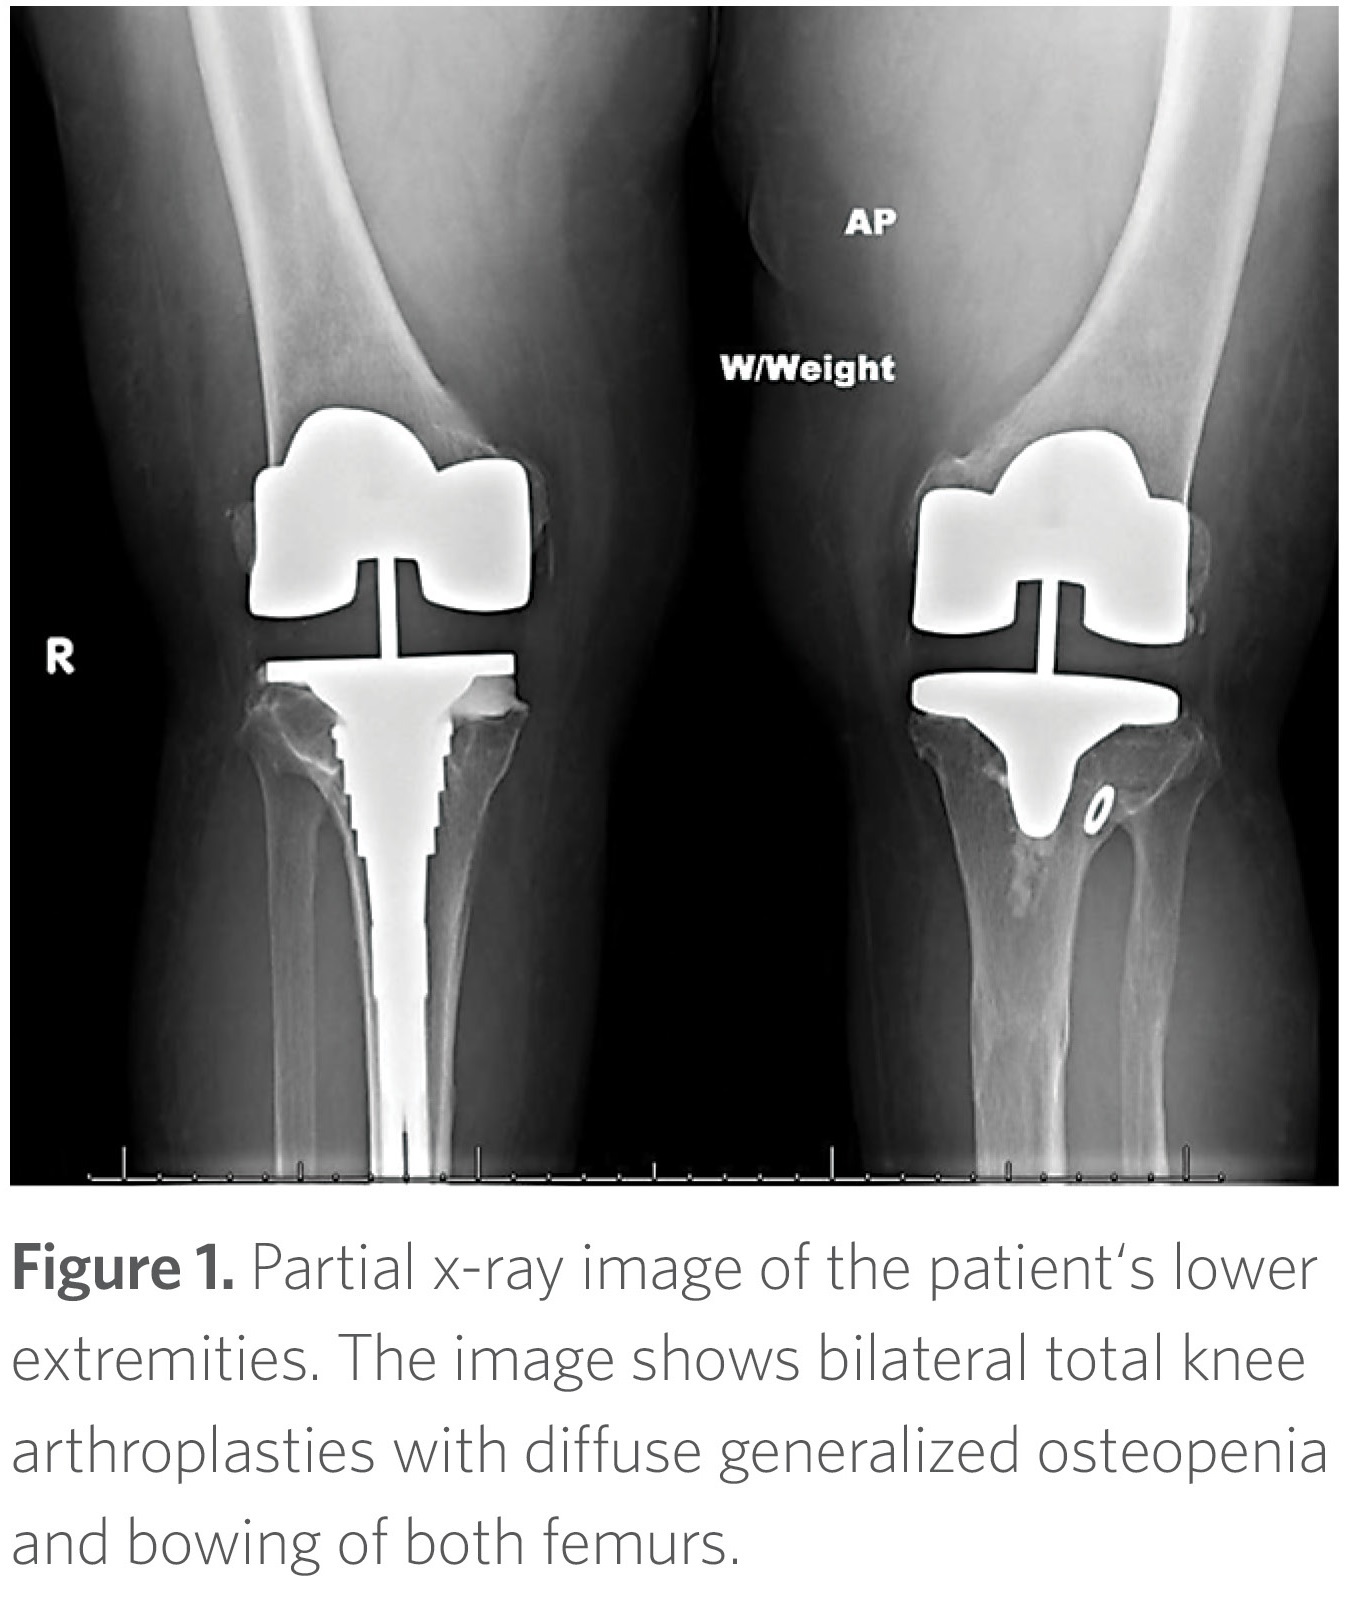

The patient began experiencing progressive and debilitating knee pain secondary to degenerative joint disease related to her bowing deformities. She eventually underwent bilateral knee replacements in her late 40s (Figure 1). She also experienced declining bone mineral density with loss of height but without fragility fractures. In addition, she developed progressive hearing loss, as well as recurrent dental abscesses since age 10, necessitating extensive dental work.

On physical exam, she had short stature (143 cm) with a disproportionally short lower segment compared to the upper segment with visible bowing deformities of her femurs. Her face was asymmetric and she had multiple fillings and healed implants on oral exam. Her spine was notable for moderate to severe scoliosis with loss of lumbar lordosis.